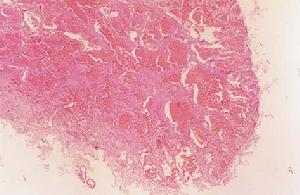

在病理切片中可見大量伴圓細胞浸潤的幼稚型結締組織,以及特別豐富的粗細不等的薄壁血管和血竇,因而被誤診為血管纖維瘤、纖維血管瘤、單純性血管瘤、毛細血管擴張性或肥大性血管瘤、或“血管肉瘤”。此外,新生物雖在臨床表現為良性,但生長極快,很容易復發,多見於女性,表明並非真性腫瘤。文獻資料記載,發生於鼻中隔軟骨及犁骨交界處的血管瘤,則可能來源於胚胎殘餘的真性腫瘤。

鼻腔及鼻竇發生的真性血管瘤分為兩種:單純性血管瘤(毛細血管瘤)及海綿狀血管瘤。文獻記載鼻部及鼻竇的海綿狀血管瘤日漸增多。文獻報導還有發生於鼻骨、上頜骨者的海綿狀血管瘤。

血管瘤按臨床表現及組織結構特徵,一般可分為毛細血管瘤、海綿狀血管瘤及蔓狀血管瘤3種,另外還有毛細血管瘤為海綿狀血管瘤的混合型。

血管瘤大小不一,可具細蒂或廣基。毛細血管瘤較小而多有蒂,海綿狀血管瘤較大而基底廣。色紅、紫或黑紅,呈圓形、卵圓形或為桑椹形。質較軟而有彈性,易出血。海綿狀血管瘤質軟,可壓縮,多發生於上頜竇的自然開口附近和下鼻甲處。腫瘤大者可壓迫竇壁,破壞骨質,侵入鄰近器官。